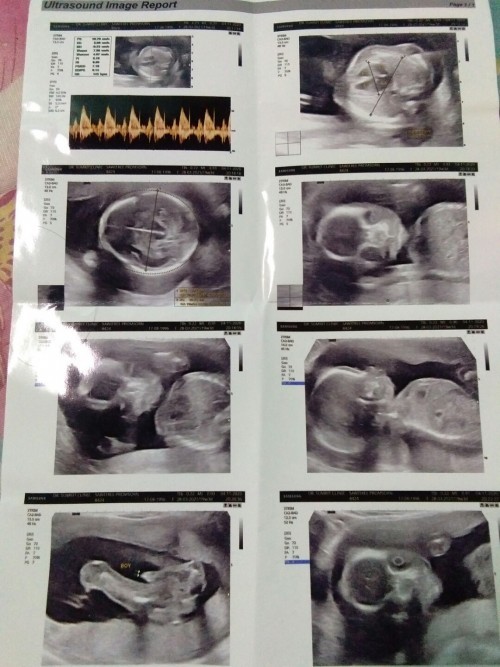

มาอวดภาพอัลตร้าซาวด์กันหน่อยแม่จ๋า 🤰🏻👼🏻 ชาย หรือ หญิง กันนะ?

3เดือน